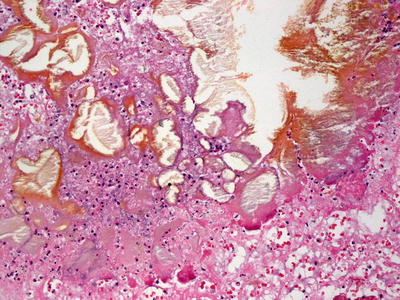

The differential diagnosis includes pancreatic panniculitis that demonstrates more extensive necrosis and calcification (Figs. 9.10 and 9.11). Alpha-1 antitrypsin deficiency-associated panniculitis is more focal than the diffuse process seen in factitial panniculitis .

Fig. 9.10

Pancreatic fat necrosis in pancreatic panniculitis results in a lobular panniculitis with abundant neutrophils

Fig. 9.11

Extensive necrosis in pancreatic fat necrosis results in cystically dilated spaces, hemosiderin deposition, and widespread calcification in late stage lesions